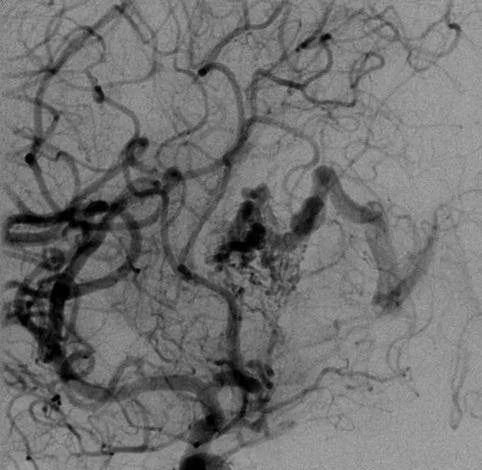

▼该AVM由ACA/PcaA分支、ACoA穿支和mPChA供血[右侧ICA造影

(a)侧位s(b)前斜位